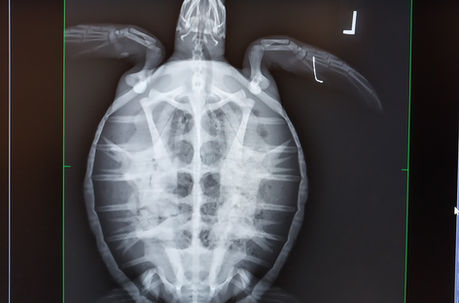

Turtle Rescues

Researchers at East Coast Biologists, Inc. are trained and permitted through the Florida Fish and Wildlife Conservation Commission (FWC) to handle live and stranded sea turtles. If you find a dead, sick, or injured sea turtle in Florida, please call FWC's 24-hour Wildlife Alert Hotline at 1-888-404-FWCC (1-888-404-3922). Click here for more information.